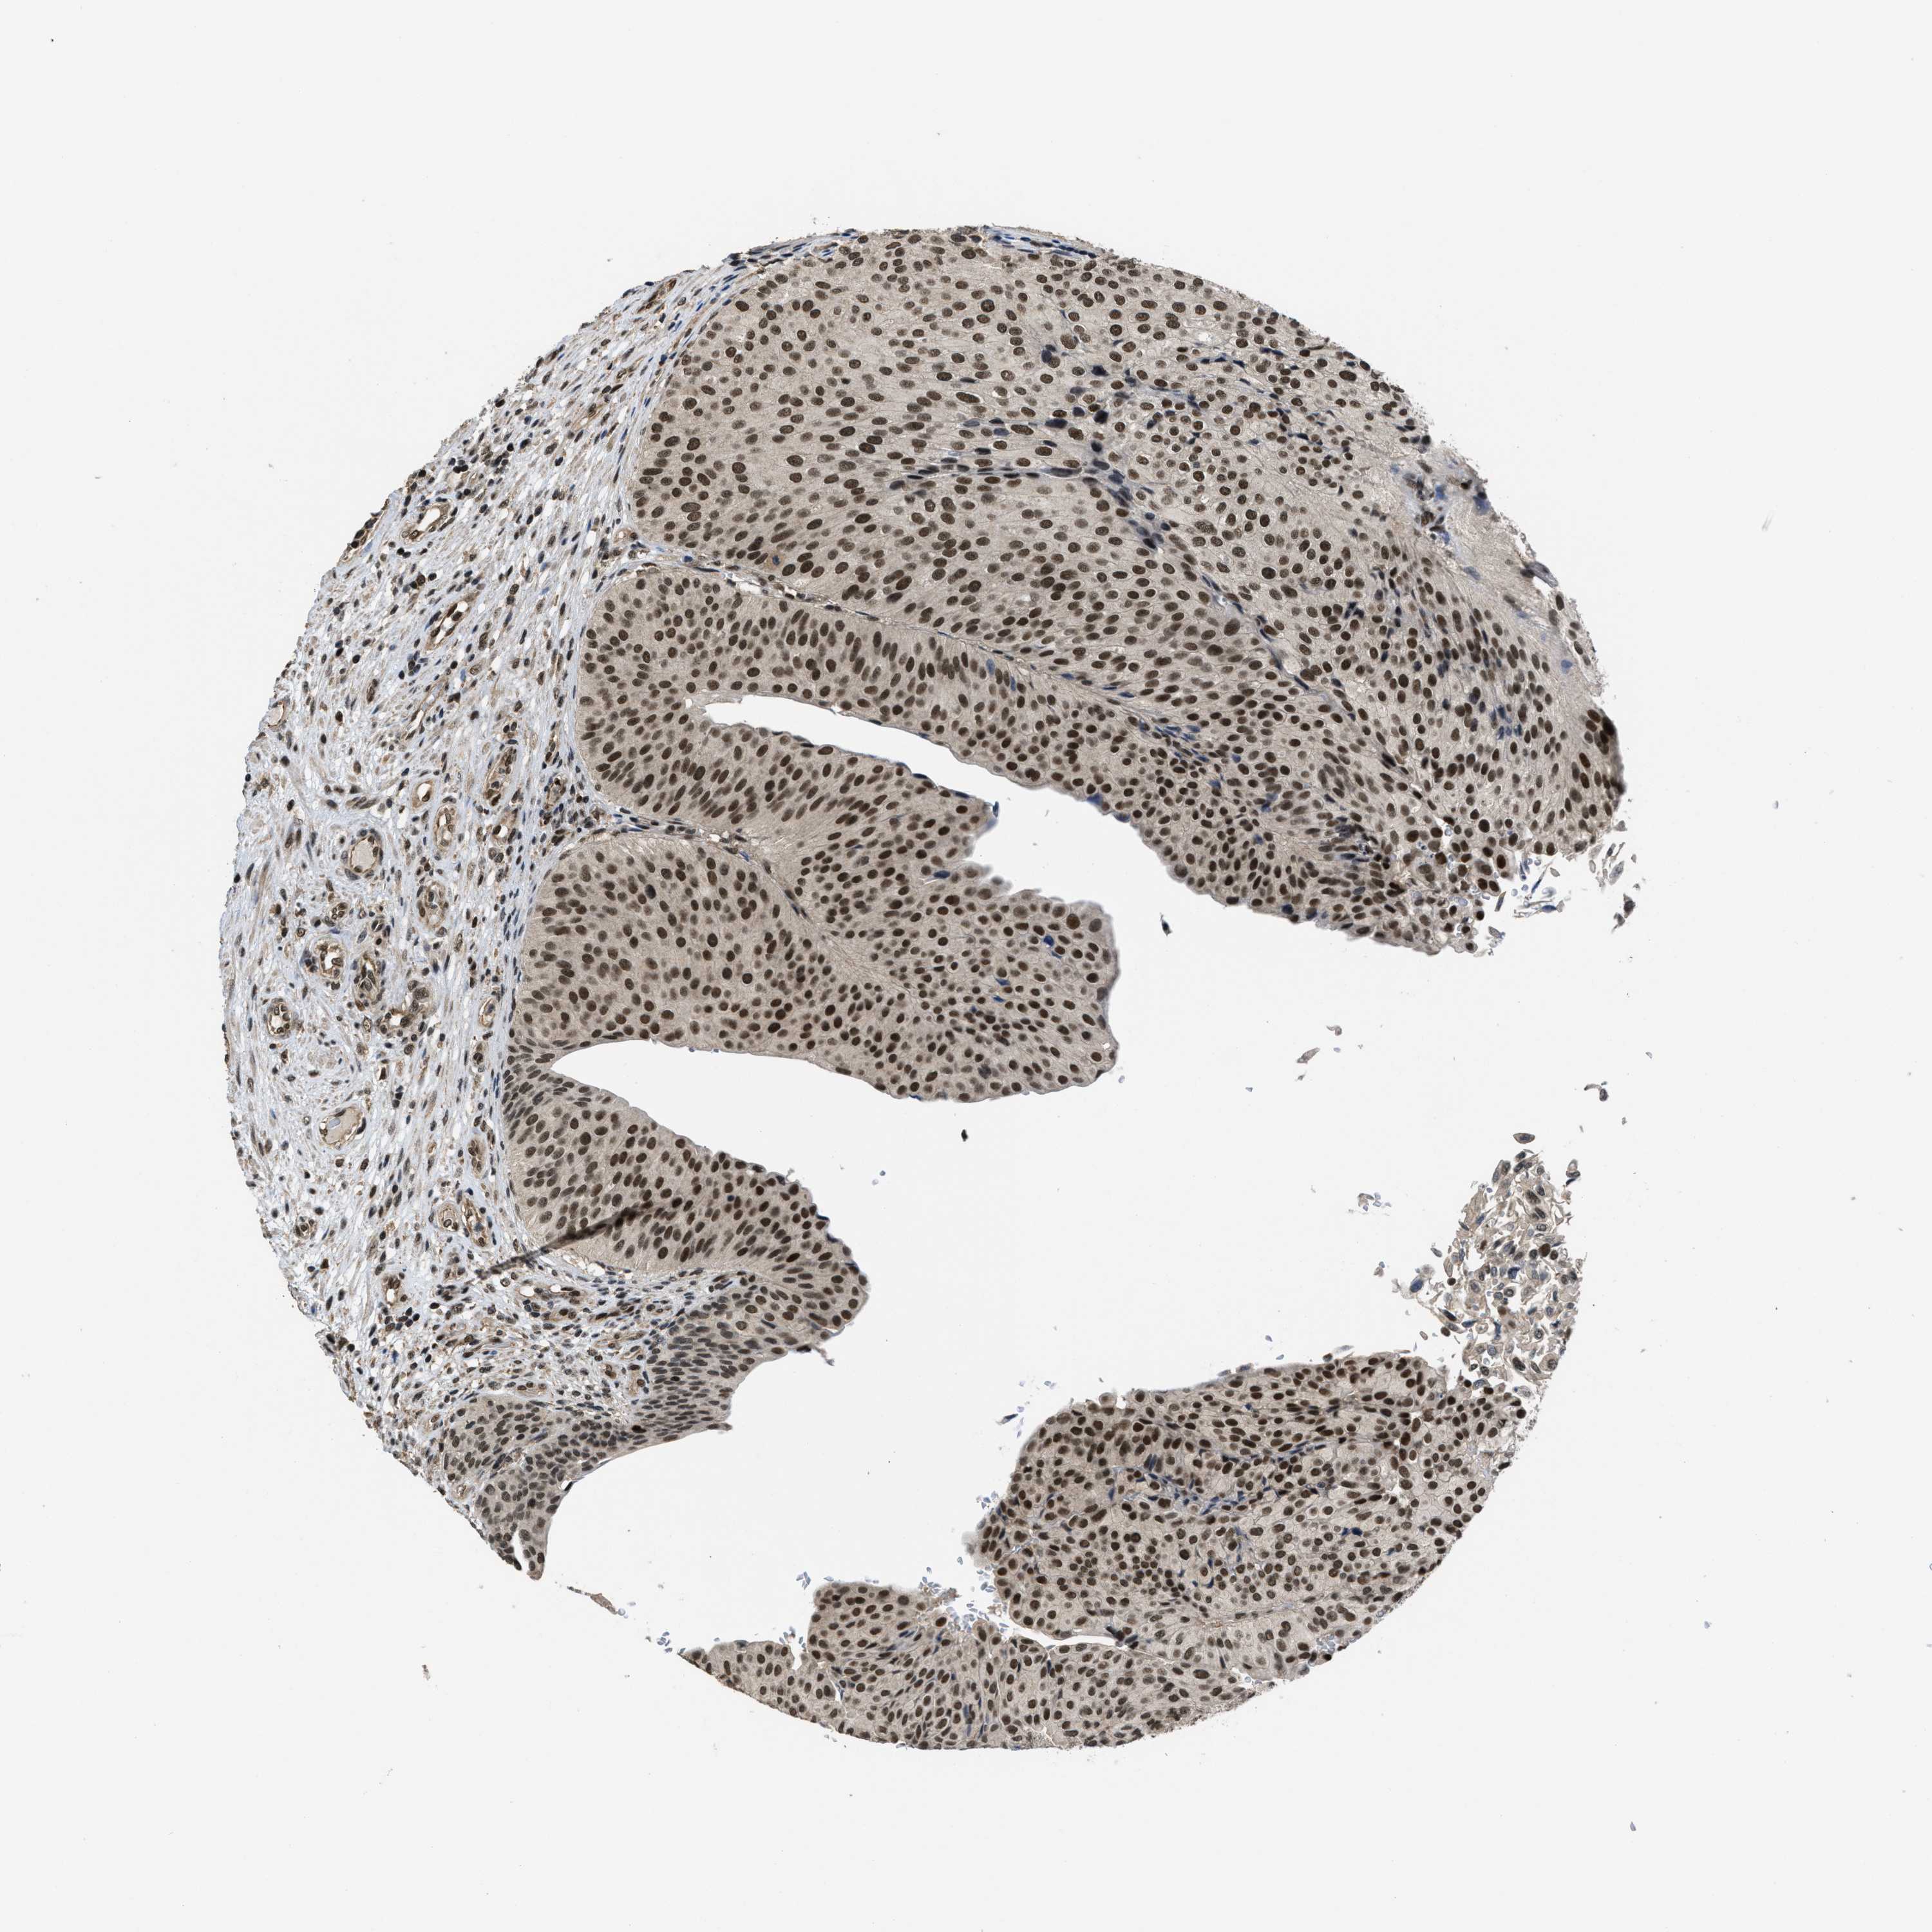

UROTHELIAL CANCER - Protein expressioni

A mouse-over function shows sample information and annotation data. Click on an image to view it in a full screen mode. Samples can be filtered based on level of antibody staining by selecting one or several of the following categories: high, medium, low and not detected. The assay and annotation is described here.

Note that samples used for immunohistochemistry by the Human Protein Atlas do not correspond to samples in the TCGA dataset.

Antibody stainingi

Antibody staining in the annotated cell types in the current human tissue is reported as not detected, low, medium, or high, based on conventional immunohistochemistry profiling in selected tissues. This score is based on the combination of the staining intensity and fraction of stained cells.

Each image is clickable and will lead to virtual microscopy that enables deeper exploration of all samples and also displays staining intensity scores, fraction scores and subcellular localization as well as patient and tissue information for each sample.

Antibody HPA011880

Antibody CAB017786

Staining

High

Medium

Low

Not detected

Intensity

Strong

Moderate

Weak

Negative

Quantity

>75%

75%-25%

<25%

None

Location

Nuclear

Cytoplasmic/membranous

Cytoplasmic/membranous,nuclear

Urothelial carcinoma, Low grade

Urothelial carcinoma, High grade